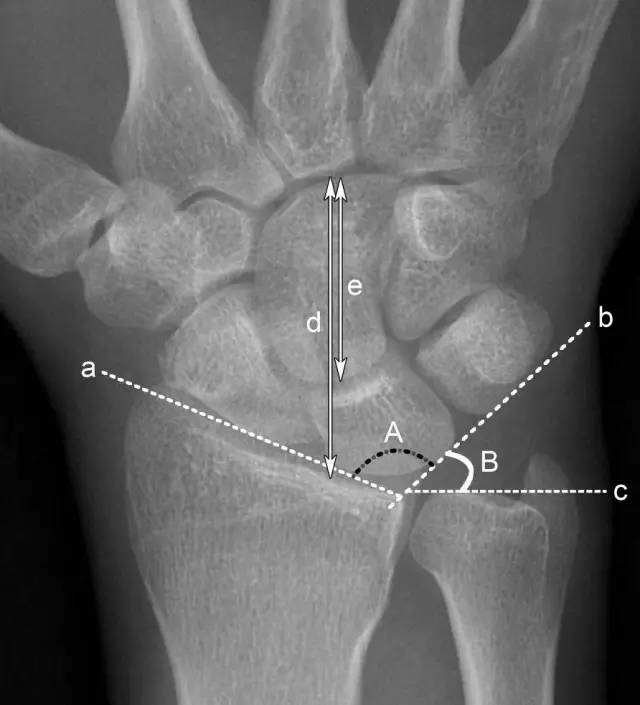

头状骨长度 a.腕骨角 b.

腕关节不稳定是指早期或迟发的因腕骨正常序列消失引起的腕部损伤